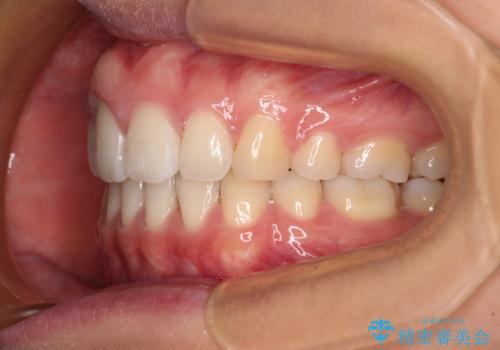

4本の歯を抜歯したことで、飛び出していた口元が引っ込み、横顔が大きく改善されました。

咬み合わせが悪化することのないようにスペースを閉じていくことができ、比較的スムーズに治療を進めることができました。